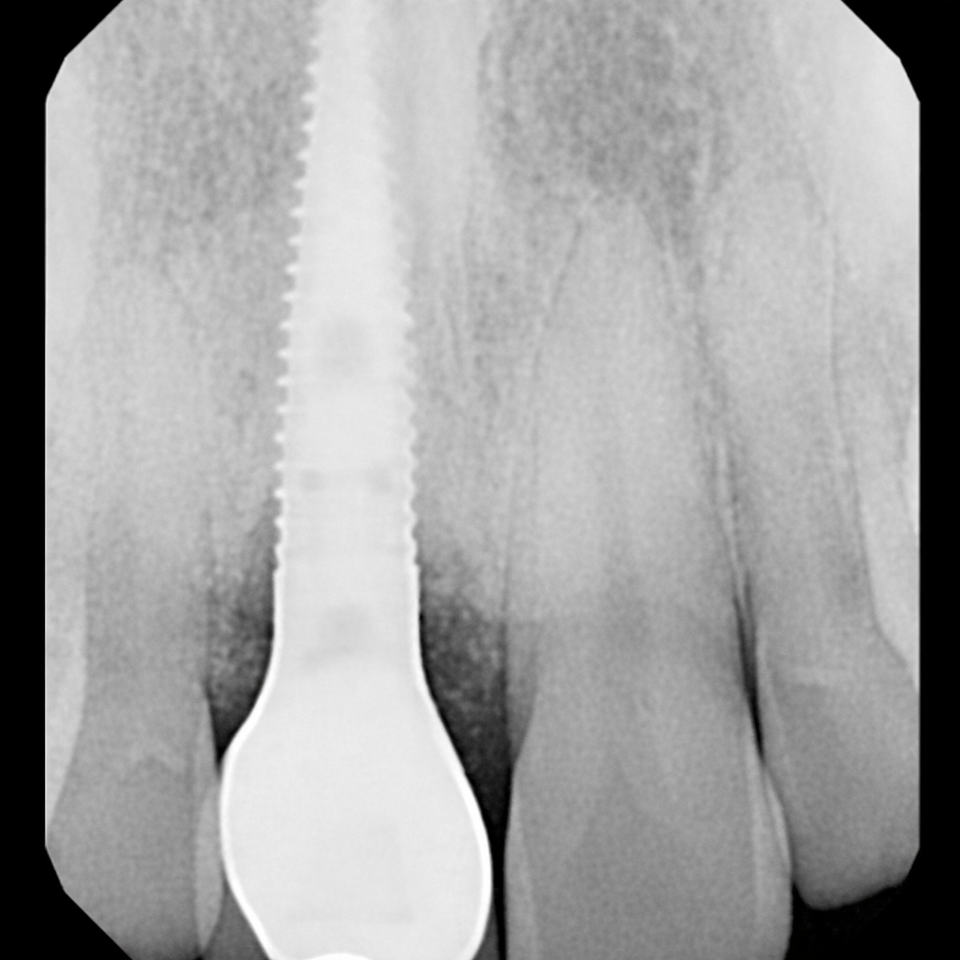

In another case, we provided emergency treatment involving root canal therapy for the upper central incisors. After careful evaluation, we placed an immediate implant for the right lateral incisor and performed a crown lengthening procedure to ensure proper restorative support.

To maintain both function and esthetics during healing, we placed a provisional bridge. After a four-month healing period, we finalized the treatment by placing custom crowns on the central incisors and restoring the implant with its permanent crown.

The result was a stable, natural-looking restoration that preserved both structure and smile aesthetics.